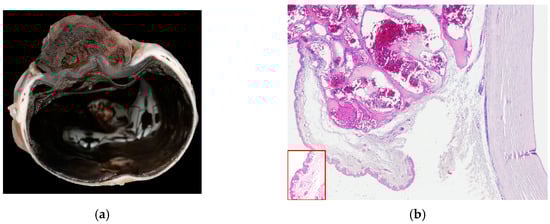

In the majority of cases, the tumor extended to the limbus (14/19) (Figure 4a), while fewer were limited to the cornea (5/19). Most neoplasms grew infiltrating the stroma (10/19), two of which (2/10) showed a stromal invasive pattern (Figure 4a and Figure 5a). Six SCCs (6/19) were exophytic, and three (3/19) were in situ SCC.

Figure 4.

(a) Horse, formalin-fixed eye globe, gross features of corneo-limbal SCC (courtesy of Dr. Riccardo Stoppini); (b) horse, eye, clinical aspect of a stromal invasive SCC (courtesy of Dr. Samuela Mazzucchelli).

Figure 5.

(a) Horse, cornea: typical features of stromal invasive SCC; neoplastic cells form islands deep in the stroma, without connection with the corneal epithelium (EE, 10×). (b) Horse, limbus: infiltrative corneo-limbal SCC; severe elastosis is recognizable in the conjunctival lamina propria (EE, 4×). Inset: Detail of the conjunctival elastosis (EE, 40×).

The degree of inflammation was equally distributed between moderate and severe (10/19 cases) and mild or absent (9/19 cases). Elastosis of the bulbar conjunctiva (Figure 5b) and acantholytic cells were evident in 9/19 cases.